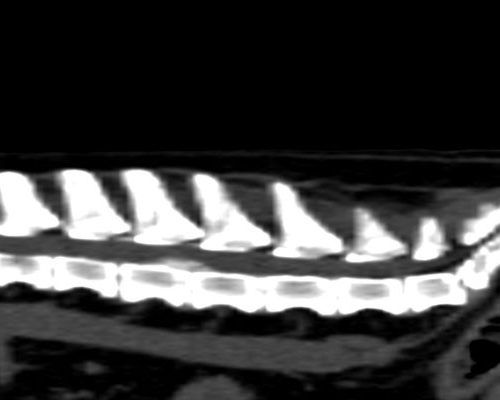

TC MULTISTRATO